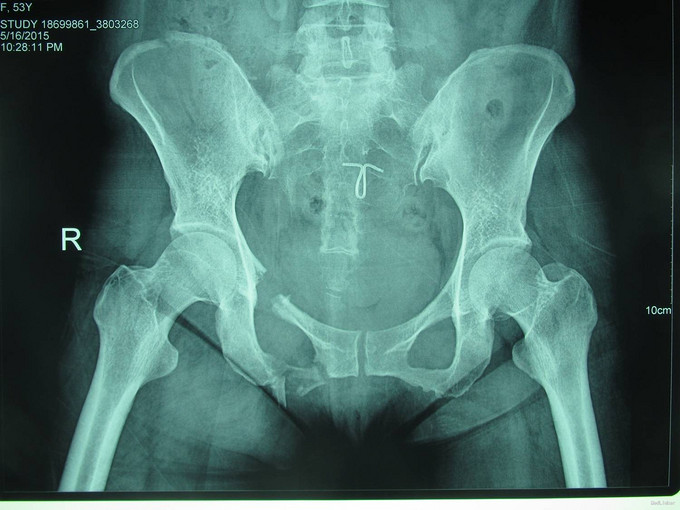

主诉:外伤后右髋部疼痛肿胀8天 现病史:患者于2015年5月16日发生车祸,伤后右髋部疼痛肿胀,下肢运动障碍,急诊120送至丹东市二医院,行骨盆平片,骨盆CT提示骨盆骨折,给予输血补液、骨牵引及留置尿管等对症治疗,急诊以“骨盆骨折”为主要诊断收入我科,患者病来无头晕头痛,无恶心呕吐,留置导尿中,大便正常。

专科查体:患者平车入病房,右侧髋部瘀斑,压痛(+),叩击痛(+),骨盆分离挤压试验(+),双下肢感觉未见异常,足趾活动可,双侧足背动脉搏动可触及。

诊断:骨盆骨折(Tile B1) 患者入院后完善检查后,全麻下行骨盆骨折切开复位钢板内固定术,术后给予抗炎,消肿,冷敷,患肢抬高等对症治疗。患者每天换药观察切口愈合情况,无红肿及渗出,待伤口14天后予以拆线治疗,予以出院,给予康复处方。